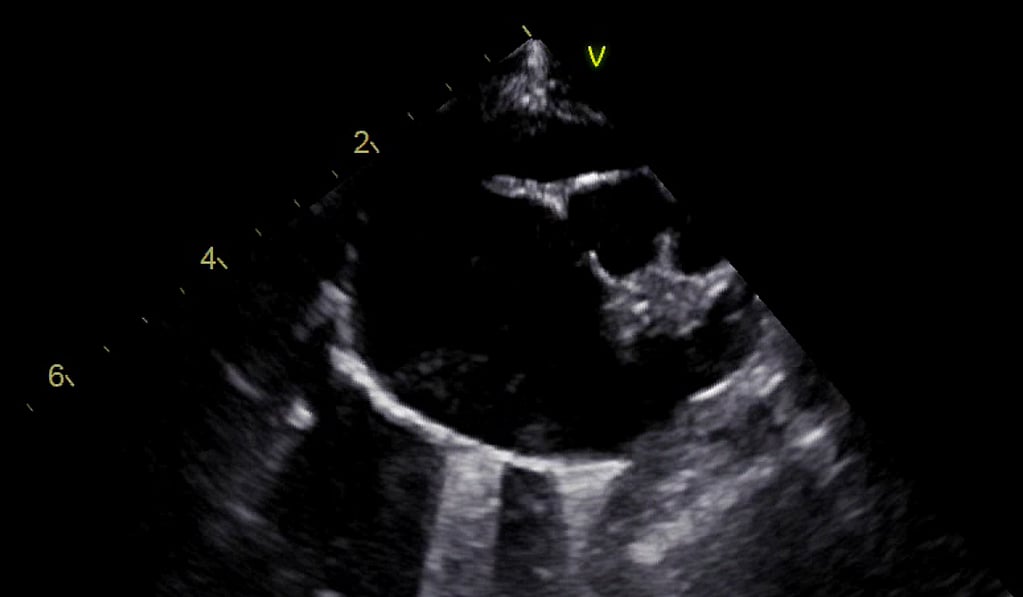

Cardiovascular POCUS

Darstellung des Herzens von rechts (stehend oder in Brust-Bauch-Lage); Einüben von Schnittebenen (von LV quer zu LA/Ao) und Darstellung der V. cava caudalis; Darstellung des pericardiaphragmatischen Fensters.